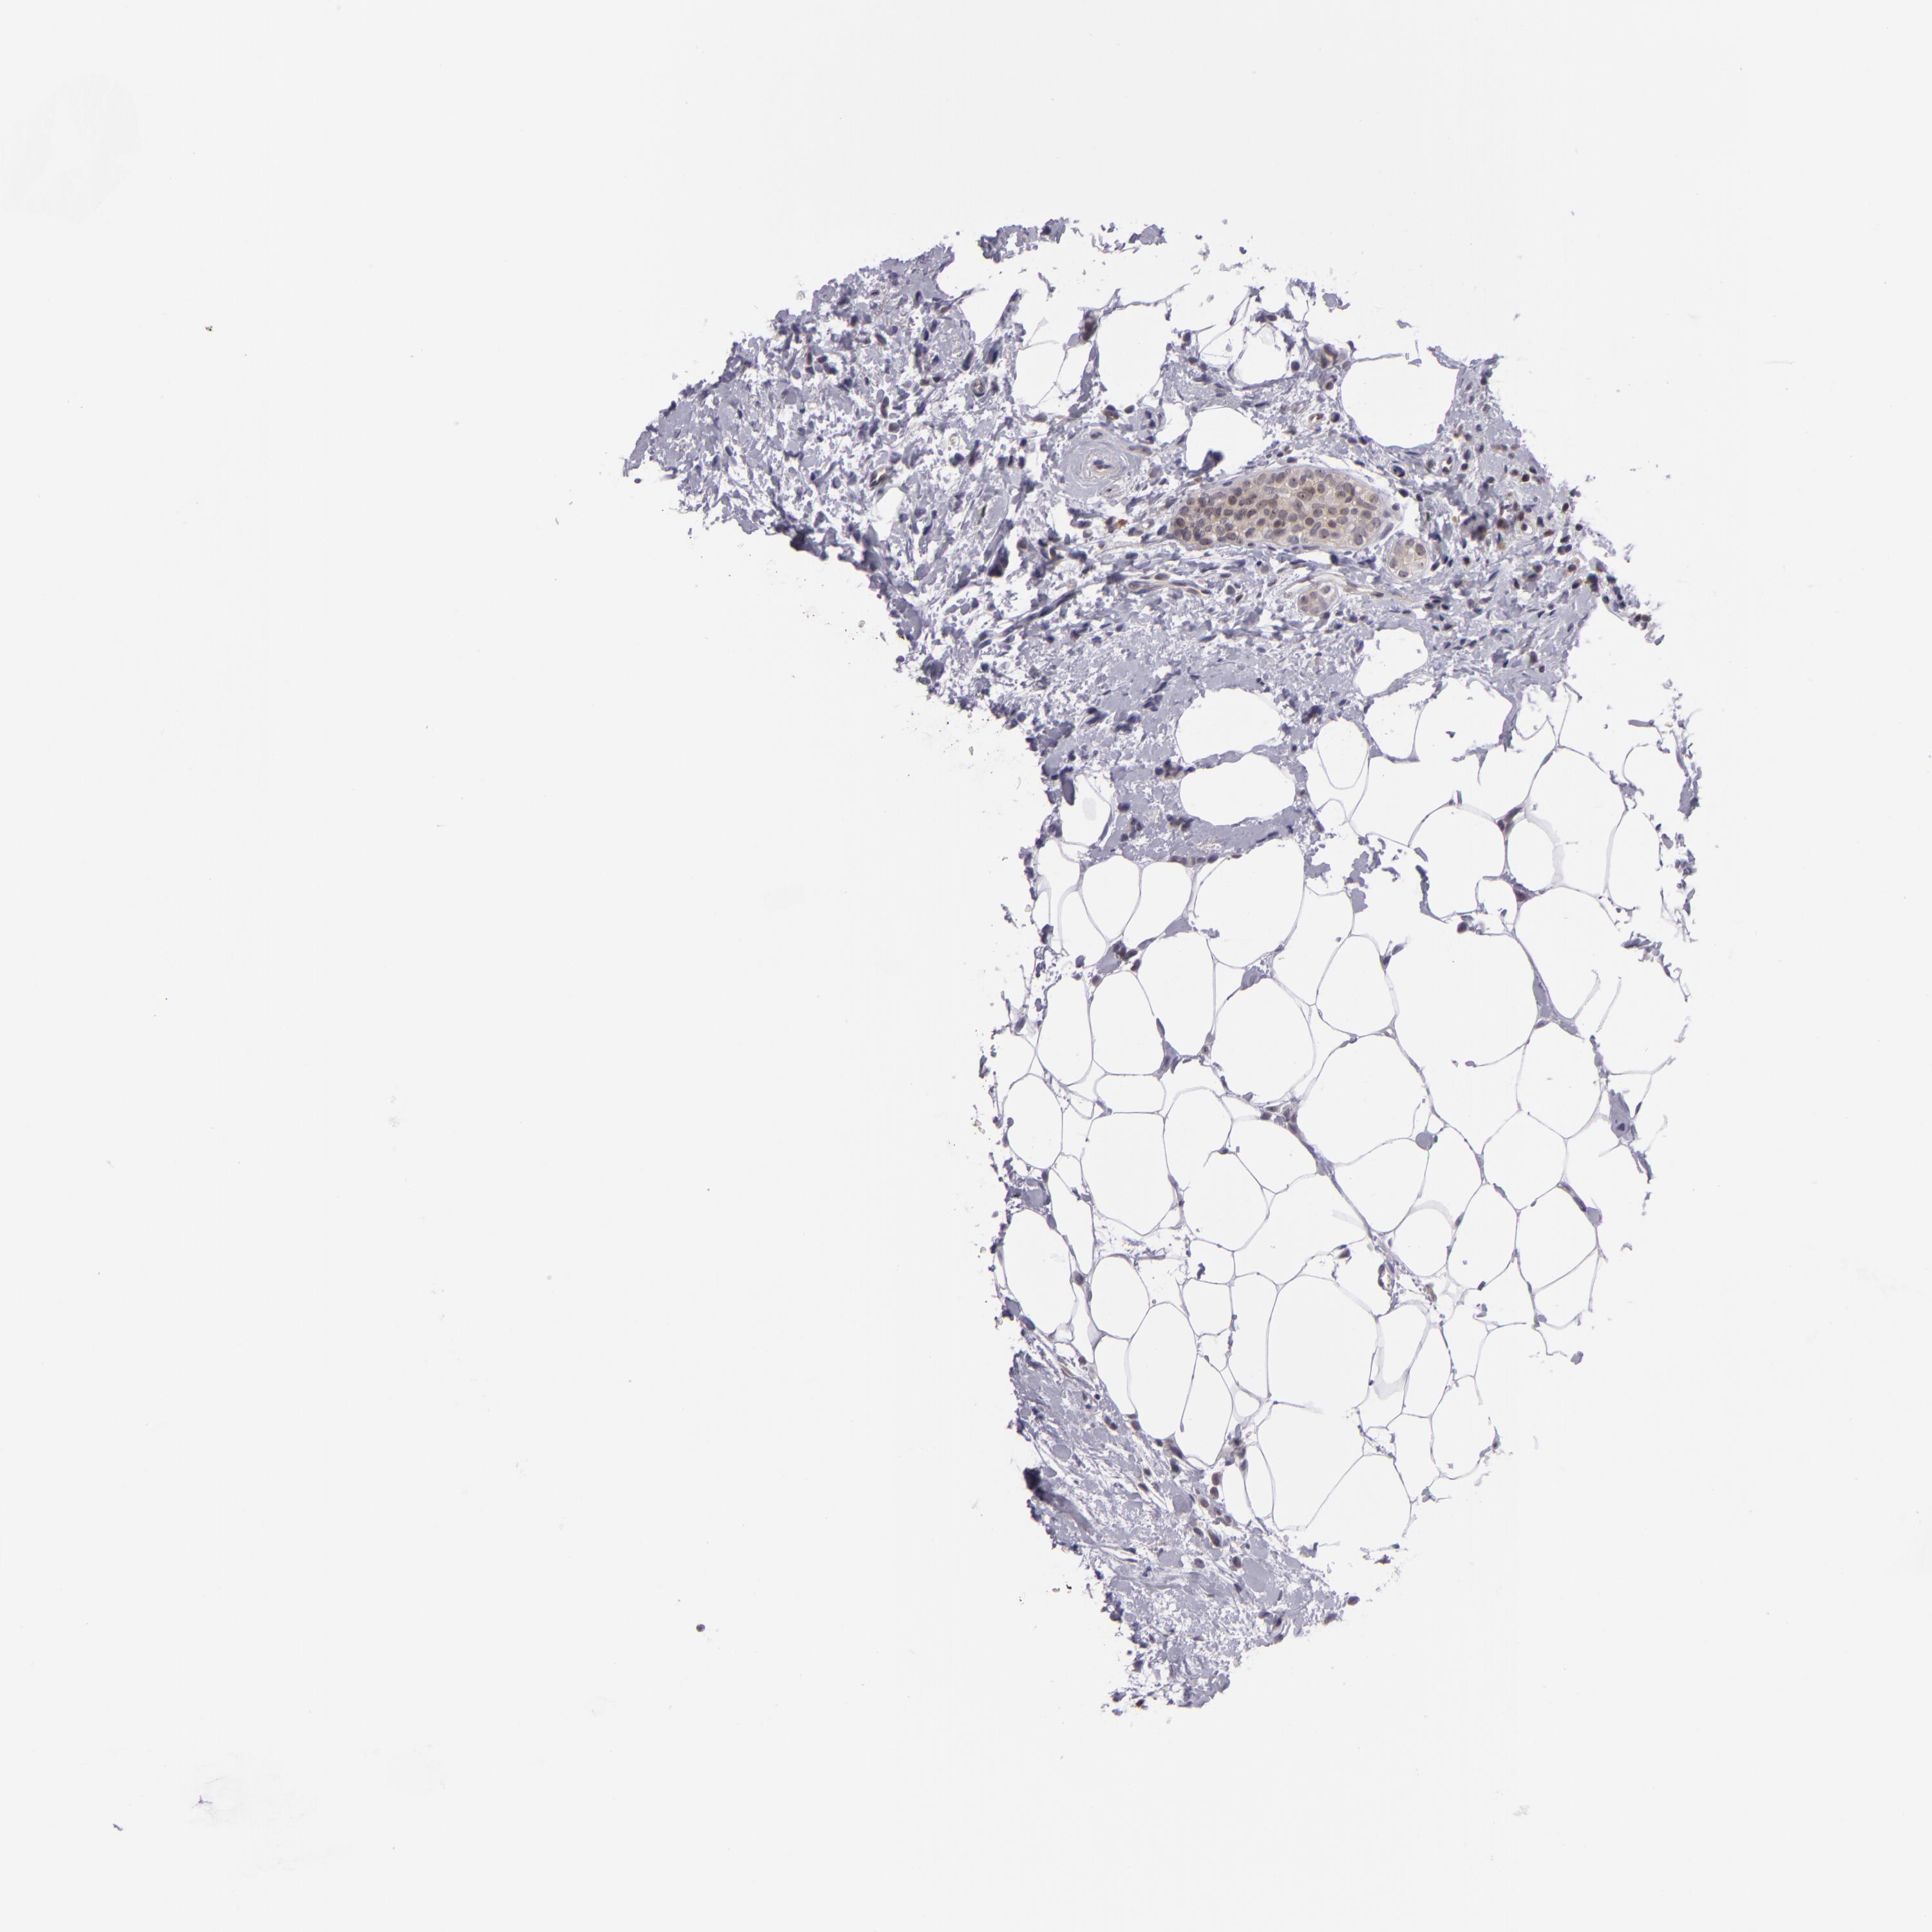

BRCA TCGA BRCA VALIDATION PROTEIN EXPRESSION

ANTIBODIES

AND

VALIDATION